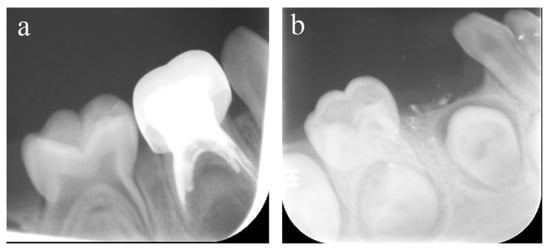

Figure 3.

#84 was treated with pulpectomy and filled with ZOE under DGA. The follow-up period was 34 months (31-month-old male child) (a) Two weeks after the operation, the radiographic showed that the filling in the distal roots was underfilled. (b) Thirty-four months after treatment, #84 was lost early, but a portion of the ZOE particles remained. The pulpectomy in #84 failed.